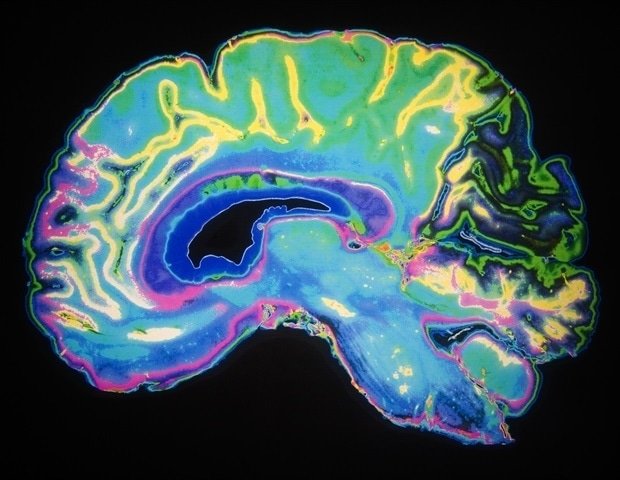

As you get better at recognizing familiar faces in a crowd, spotting typos at a glance, and predicting your next move, the game-sensing neurons in your brain become more attuned to sharing information rather than acting independently. That’s the conclusion of a new study by researchers at the University of Rochester and its Del Monte Neuroscience Institute. scienceThis challenges the long-standing assumption in neuroscience that learning increases efficiency by minimizing repetitions between neural signals.

The study, led by Shijiao Liu, a graduate student in the labs of faculty members Ralph Hefner and Adam Snyder in the Department of Brain and Cognitive Sciences, shows that learning actually increases shared activity between neurons. The discovery could provide insights into learning disabilities and lead to more flexible, human-like artificial intelligence tools.

“The dominant view in neuroscience is that learning allows neurons to act more independently, making the brain more efficient and able to read information more cleanly,” Liu says. “Our findings support the alternative idea that the brain’s sensory cortex is not just passively encoding the world, but actively performing inferences by combining what comes in and the brain’s learned expectations.”

For decades, researchers believed that learning reduces shared activity between neurons, streamlining the way the brain processes information and allowing it to be read more efficiently. This idea has shaped how researchers think about everything from perception to decision-making.

But the work of Liu, Haefner, Snyder, and their team suggests a different mechanism. As learning progresses, neurons become less independent and more coordinated, increasing the amount of information they share, especially when the brain is actively working on a task and making decisions.

This adjustment reflects the brain’s increasing reliance on internal expectations. As learning progresses, feedback from higher brain regions appears to shape how sensory neurons respond, allowing them to incorporate both incoming information and what the brain has learned from past experiences into perception.

The researchers tracked the activity of the same small network of neurons in the visual cortex over several weeks as the subjects learned to distinguish between different visual patterns. The researchers measured whether neurons became more independent or shared more information as learning progressed.

The researchers found that before learning, neurons work mostly independently. But as the subjects honed their visual skills, the neurons began to behave more like a well-trained sports team, communicating and cooperating in a coordinated way.

Importantly, this coordination effect appeared only when subjects were actively performing the task and making decisions based on what they saw. If they viewed the same image passively without having to respond, the effect disappeared.

The neurons most important to the task showed the greatest boost in coordination, especially at the moment a decision was made.

However, these are flexible changes, not permanent changes. The researchers believe that these changes are guided by feedback signals from higher brain regions, allowing neurons to adjust their behavior on the fly depending on the task.

The results support the growing idea in neuroscience that the brain is more than a simple conveyor belt transmitting information forward. Instead, it constantly blends what we see with what we expect to see, creating a richer, more informed picture of the world. And that mixing requires groups of neurons to work together rather than separately.